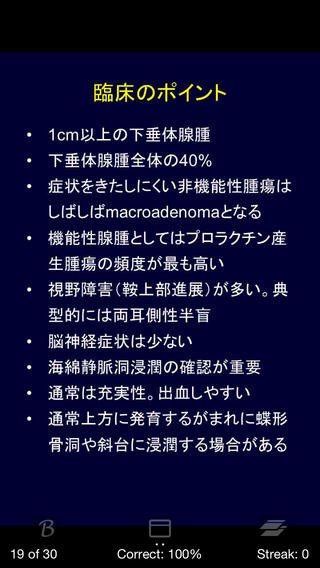

5.脳腫瘍日常臨床(1,400円)

引用元:https://itunes.apple.com/jp/app/id596370666?mt=8&ign-mpt=uo%3D4

レジデントの先生方、専門医の先生方を対象としたアプリです。

代表的な脳腫瘍30疾患に対するQ&Aと参照用データが、

全9章、180ページにわたって収録されています。